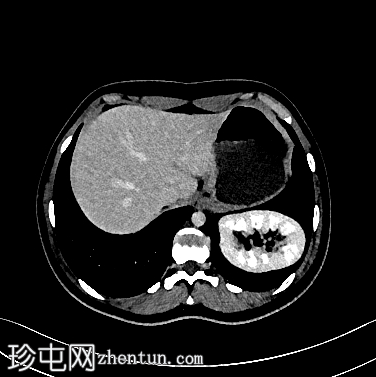

冠状位增强扫描

门静脉期

左侧Bochdalek疝,大小为8.7 x 7.5 cm,疝颈长3.2 cm。左肾位于胸腔内(Bochdalek疝伴胸内肾),无并发症。左肾旋转不良(过度旋转),肾门朝向后方,肾血管位于后方。肾血管起源正常。肾脏大小为8.6 x 5.8 x 6.1 cm,体积、实质和功能均正常。输尿管膀胱连接处位置正常。未见结石或肾积水。

右肾位置正常,大小正常(头尾径 9.5 cm),肾实质和功能均正常。未见结石或肾积水。